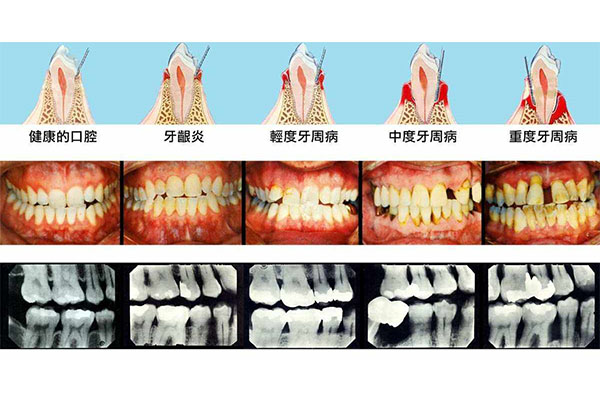

牙疼不仅影响睡眠,还会让你在吃饭时感到痛苦。尤其是中老年人,牙齿缺失或松动的问题更加明显,吃硬食或冷热食物时都会引发疼痛。长期下去,不仅会影响营养吸收,还会降低生活质量。

牙疼的偏方虽然在一定程度上可以缓解疼痛,但并不能从根本上解决问题。长期依赖偏方可能会延误治疗,导致牙齿问题更加严重。因此,建议在使用偏方的同时,尽快寻求专业的牙齿修复服务。